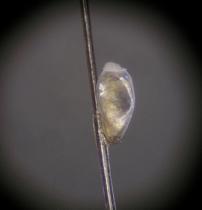

- 成虫は見つけにくいので、髪の毛についた卵を見つけることが大切です。

卵は、大きさが約1mmで、色は乳白色です。ヘアーキャスト(フケの一種)と見間違えやすいので気をつけましょう。

見分けるために、指ではさんで引っ張ってみましょう。ヘアーキャストなら簡単に動きますが、卵であればなかなか動きません。